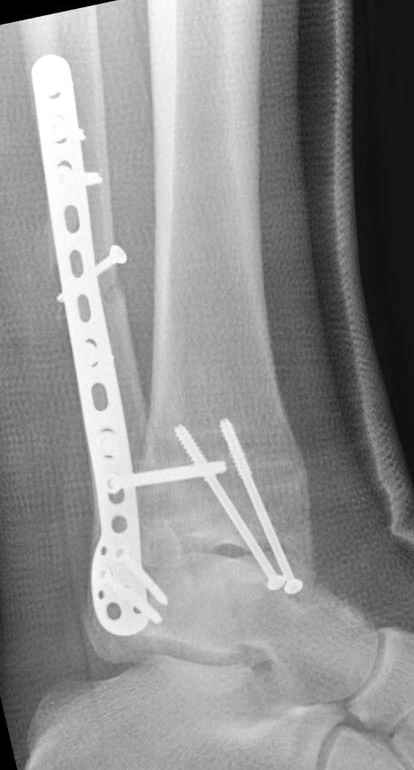

Недавний случай, больной 56 лет получил политравму в Англии, после переведен в США, где его успешно лечил местный ортопед, огромная статья в газете об успешной операции, своеобразный пиар, из-за того, что больной был американский пожарник на пенсии, и за его переезд было заплачено международным пожарным союзом, короче по другим показаниям перевели больного в наш университетский госпиталь.

После 5-6 недели после травмы сделана повторная операция, обошлись без удлинения малоберцовой.